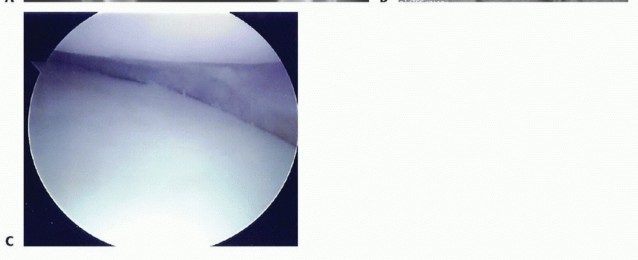

TECH FIG 2 • Lateral meniscal approach and tibial preparation. A,B. Creation of small trough between the anterior and posterior horn attachments. C. Rasping recipient site (visualized through medial portal). D,E. Tibial recipient site (dovetail trough) preparation. F. Posterolateral exposure. 2. ## Delivery and Fixation of Lateral Meniscus

Matching the anterior cortices (graft and recipient) and bringing the knee through a range of motion will assist in final AP positioning. Visualizing the meniscus' position arthroscopically will confirm proper seating of the graft (

TECH FIG 3D,E

).

Place additional inside-out meniscal sutures with the suture cannula placed in the anteromedial portal. The scope is placed into the miniarthrotomy (

TECH FIG 3F,G

Additional anterior sutures can be placed through the anterior arthrotomy using standard open suturing techniques.

Tie the sutures with the knee in flexion (lateral transplants).

TECH FIG 3 •

(continued)

D. Lateral meniscus bone bridge delivered into the tibial trough. E. Meniscus reduced under condyle. F. Placing inside-out sutures. G. Final meniscus transplant. 3. ## Medial Meniscus Graft Preparation